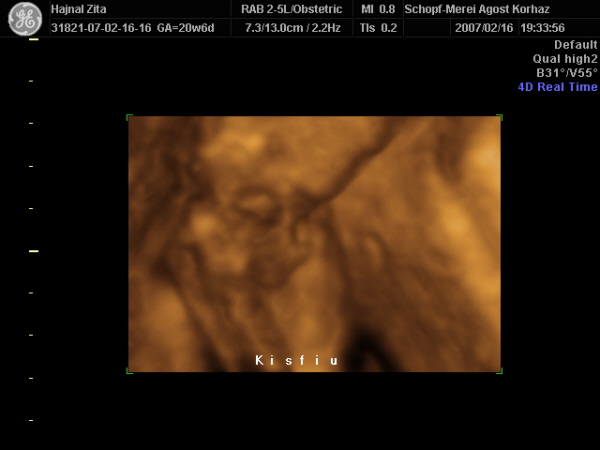

Szóval úgy tűnik még egy pöcsös lesz a családban?